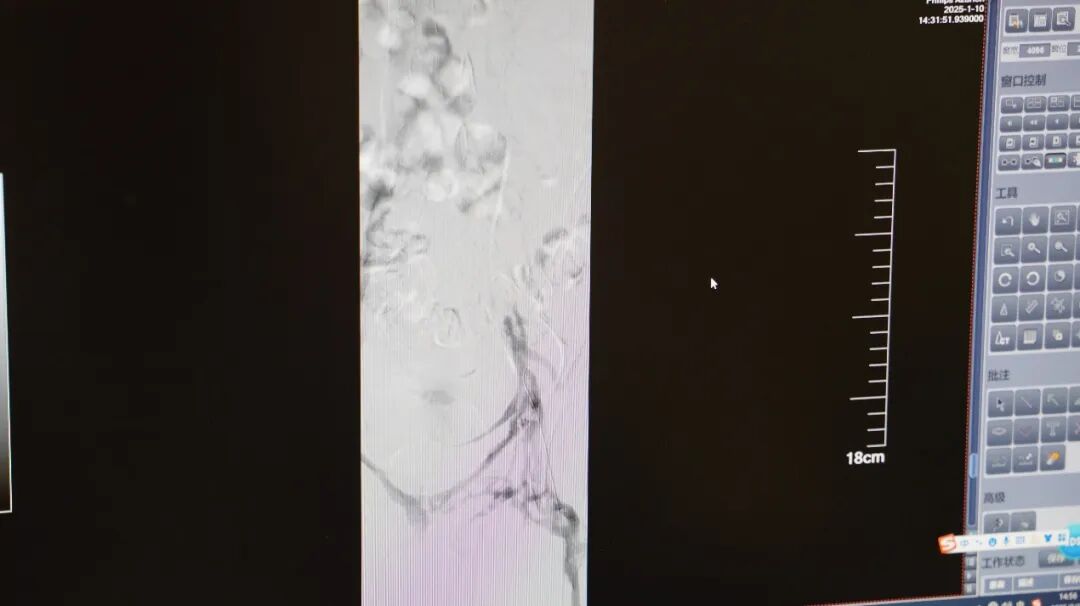

据了解,小徐临近毕业,连续数周每天久坐超8小时赶论文,其间缺乏活动且饮水不足,“我平时确实很少运动,尤其是最近,除了睡觉、吃饭、上厕所几乎都在坐着,吃得也不太健康。”经抗凝治疗和介入手术,小徐的病情得以控制,但回述起这段经历,小徐还是有点后怕。

医生发现王大哥的左腿比右腿粗了一大圈,颜色青紫,诊断其为深静脉血栓中较严重的一种类型“股青肿”,需立即手术,否则有截肢风险。术后,王大哥腿部肿胀明显缓解。